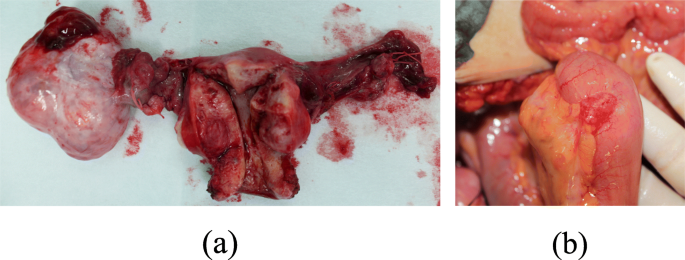

As the above findings suggested, the tumor could be either primary or secondary ovarian cancer. Therefore, we decided to perform surgery to allow for pathological examination. We performed total abdominal hysterectomy, bilateral salpingo-oophorectomy, and partial omentectomy. There was a fist-sized, lobular, cystic tumor in the right adnexa. The right ovarian tumor measured 8.5 cm in diameter, had a lobular interior, and was primarily mucinous with some solid portions (Fig. 3a). Ascites was absent, and the uterus and left adnexa appeared normal. During surgery, we found a cherry-sized tumor in the ileum, located on the 20-cm mouth side from the ileocecum. Subsequent ileal resection was performed. The ileum tumor measured 2.5 cm in diameter and showed papillary growth in the lumen (Fig. 3b).